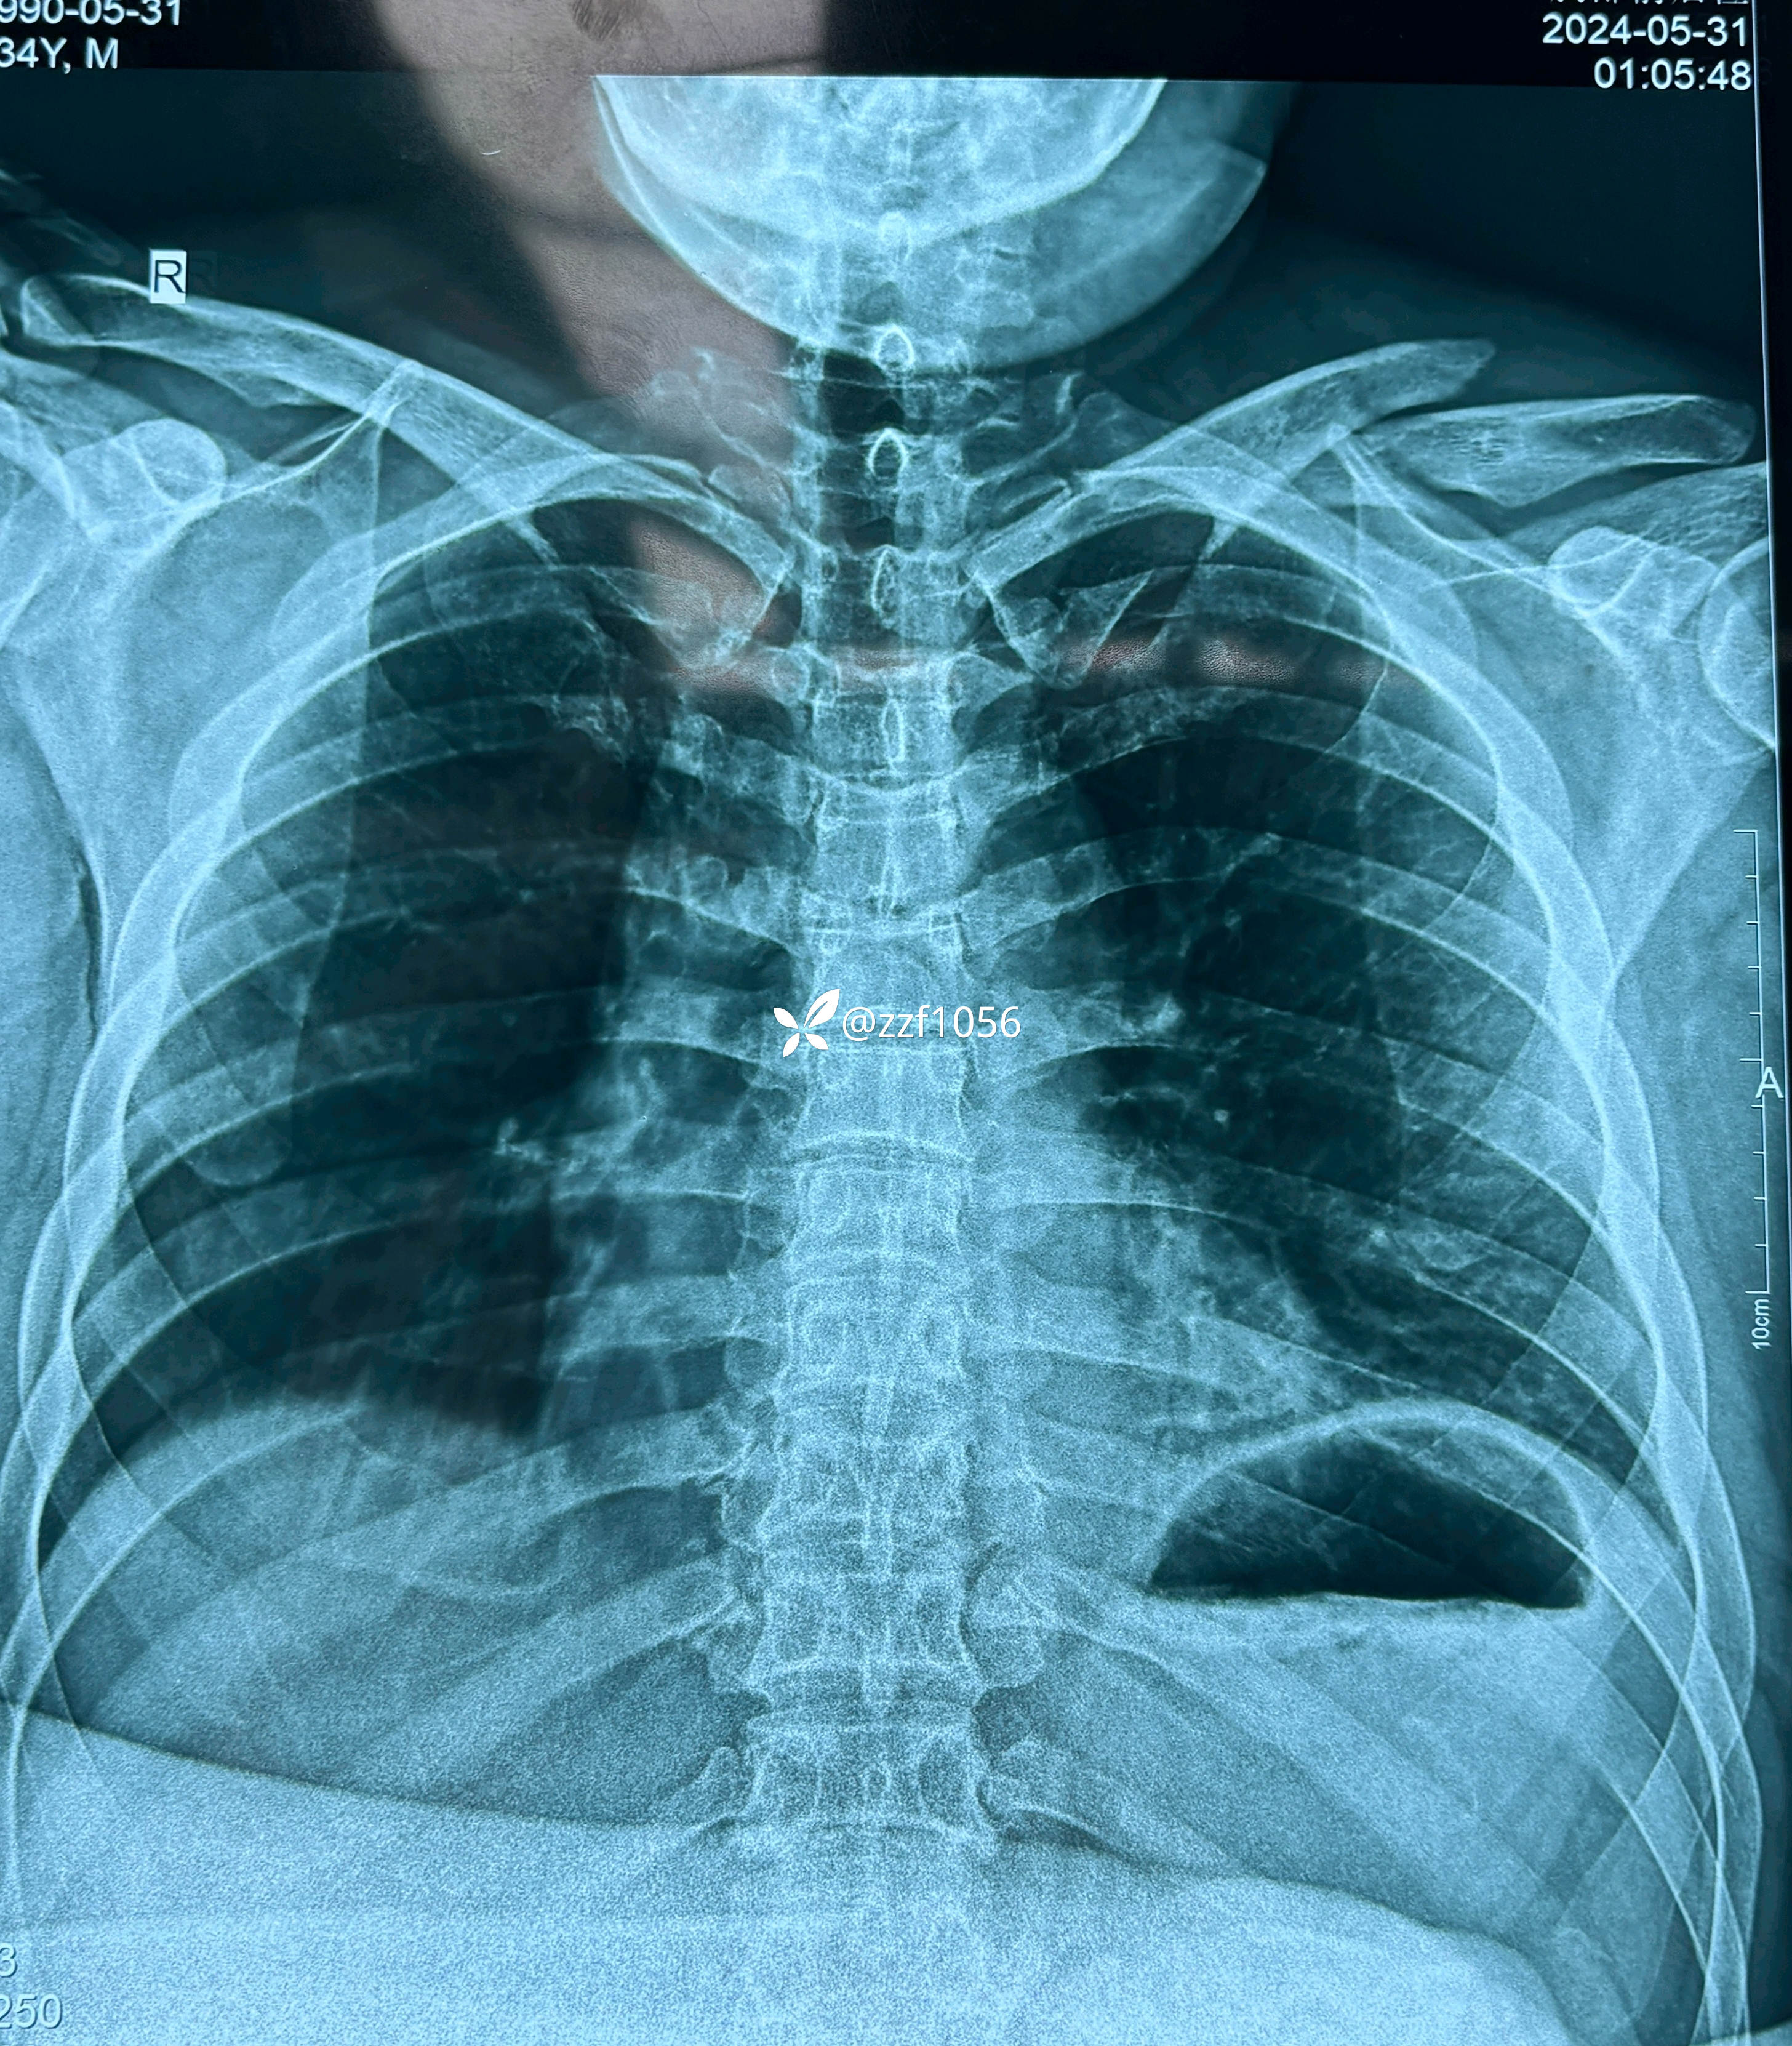

患者男性,34岁,摔伤左肩肿痛致左侧锁骨骨折在外院住院1天准备手术

完善相关检查,无手术禁忌,虽费用紧凑,但该做还得做啊,拟定第二天手术。